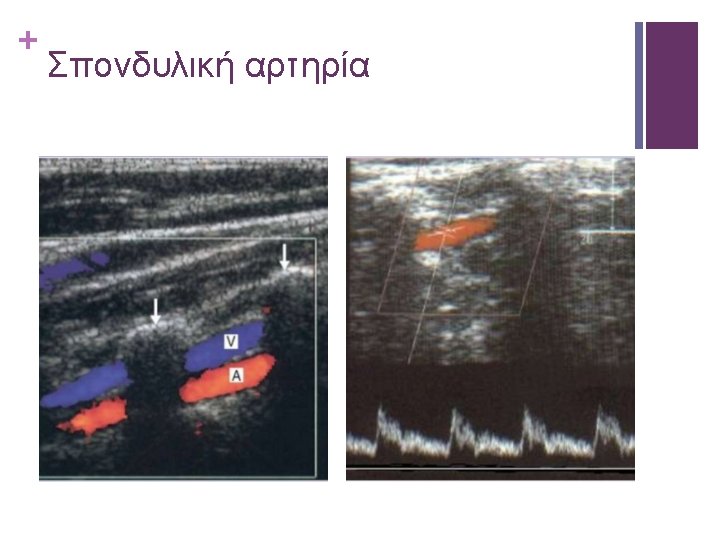

+ St. Mary’s ratio: ICAPSV / CCACCA sensitivity specificity PPV NPV accuracy 0. 92 0. 93 0. 91 0. 92